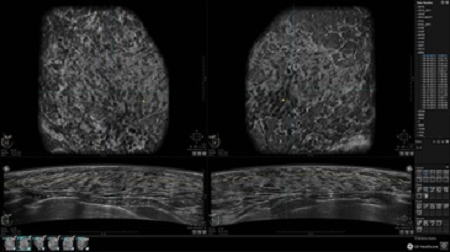

• Отображение объемных 3D ультразвуковых изображений, которые состоят из традиционных поперечных и воссозданных коронарных и сагиттальных проекций

• Возможность отображения полного 3D изображения

• Многооконный просмотр: 4 - 12 изображений

• Стандартизованная ориентация изображения: «толстый срез» в коронарной плоскости; поперечная; сагиттальная плоскость; радиальный и антирадиальный поворот изображения; просмотр исключительно области интереса

• Одновременный просмотр двух изображений для сопоставления в коронарной плоскости